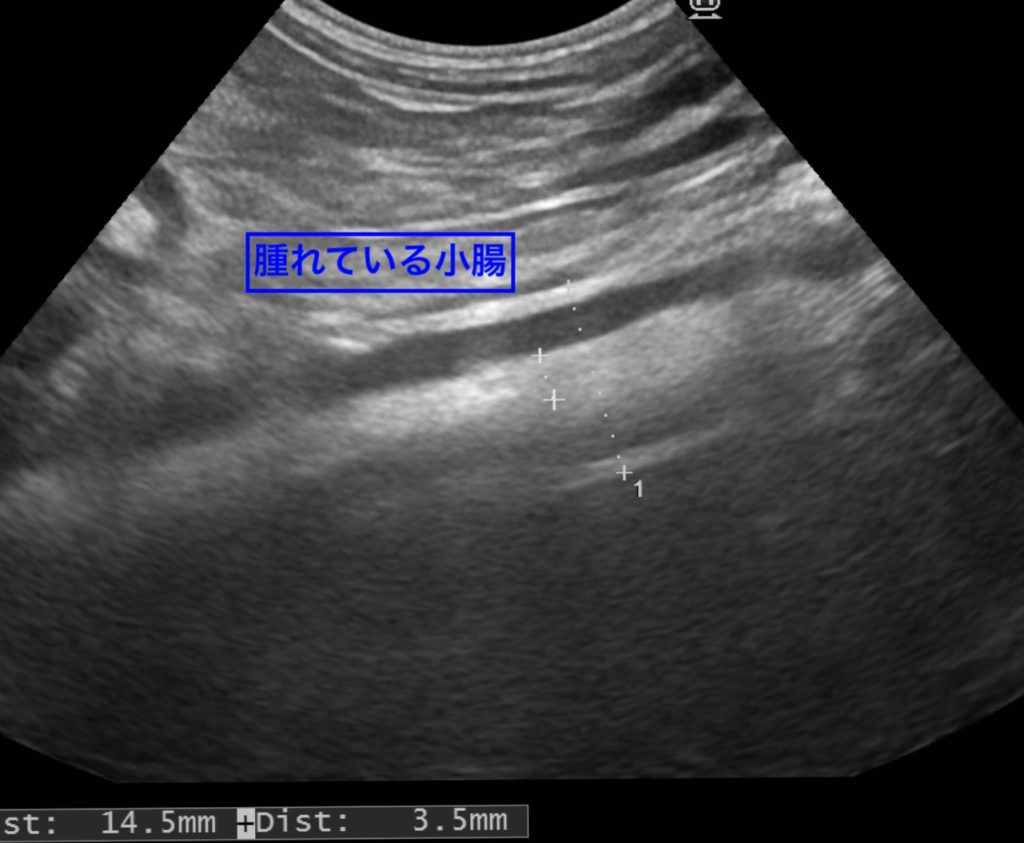

下痢がある場合には、小腸が肥厚(腫れている)していることが多いです。

炎症を伴っていることが多く、正常な小腸と比べると、内部構造を観察しにくいことが特徴です。

今回ご紹介した子は、内視鏡検査にて『炎症性腸疾患(IBD)』の診断がでています。

*正常な小腸の2倍(14.3mm)に肥厚していますが、悪性腫瘍の診断ではありませんでした。